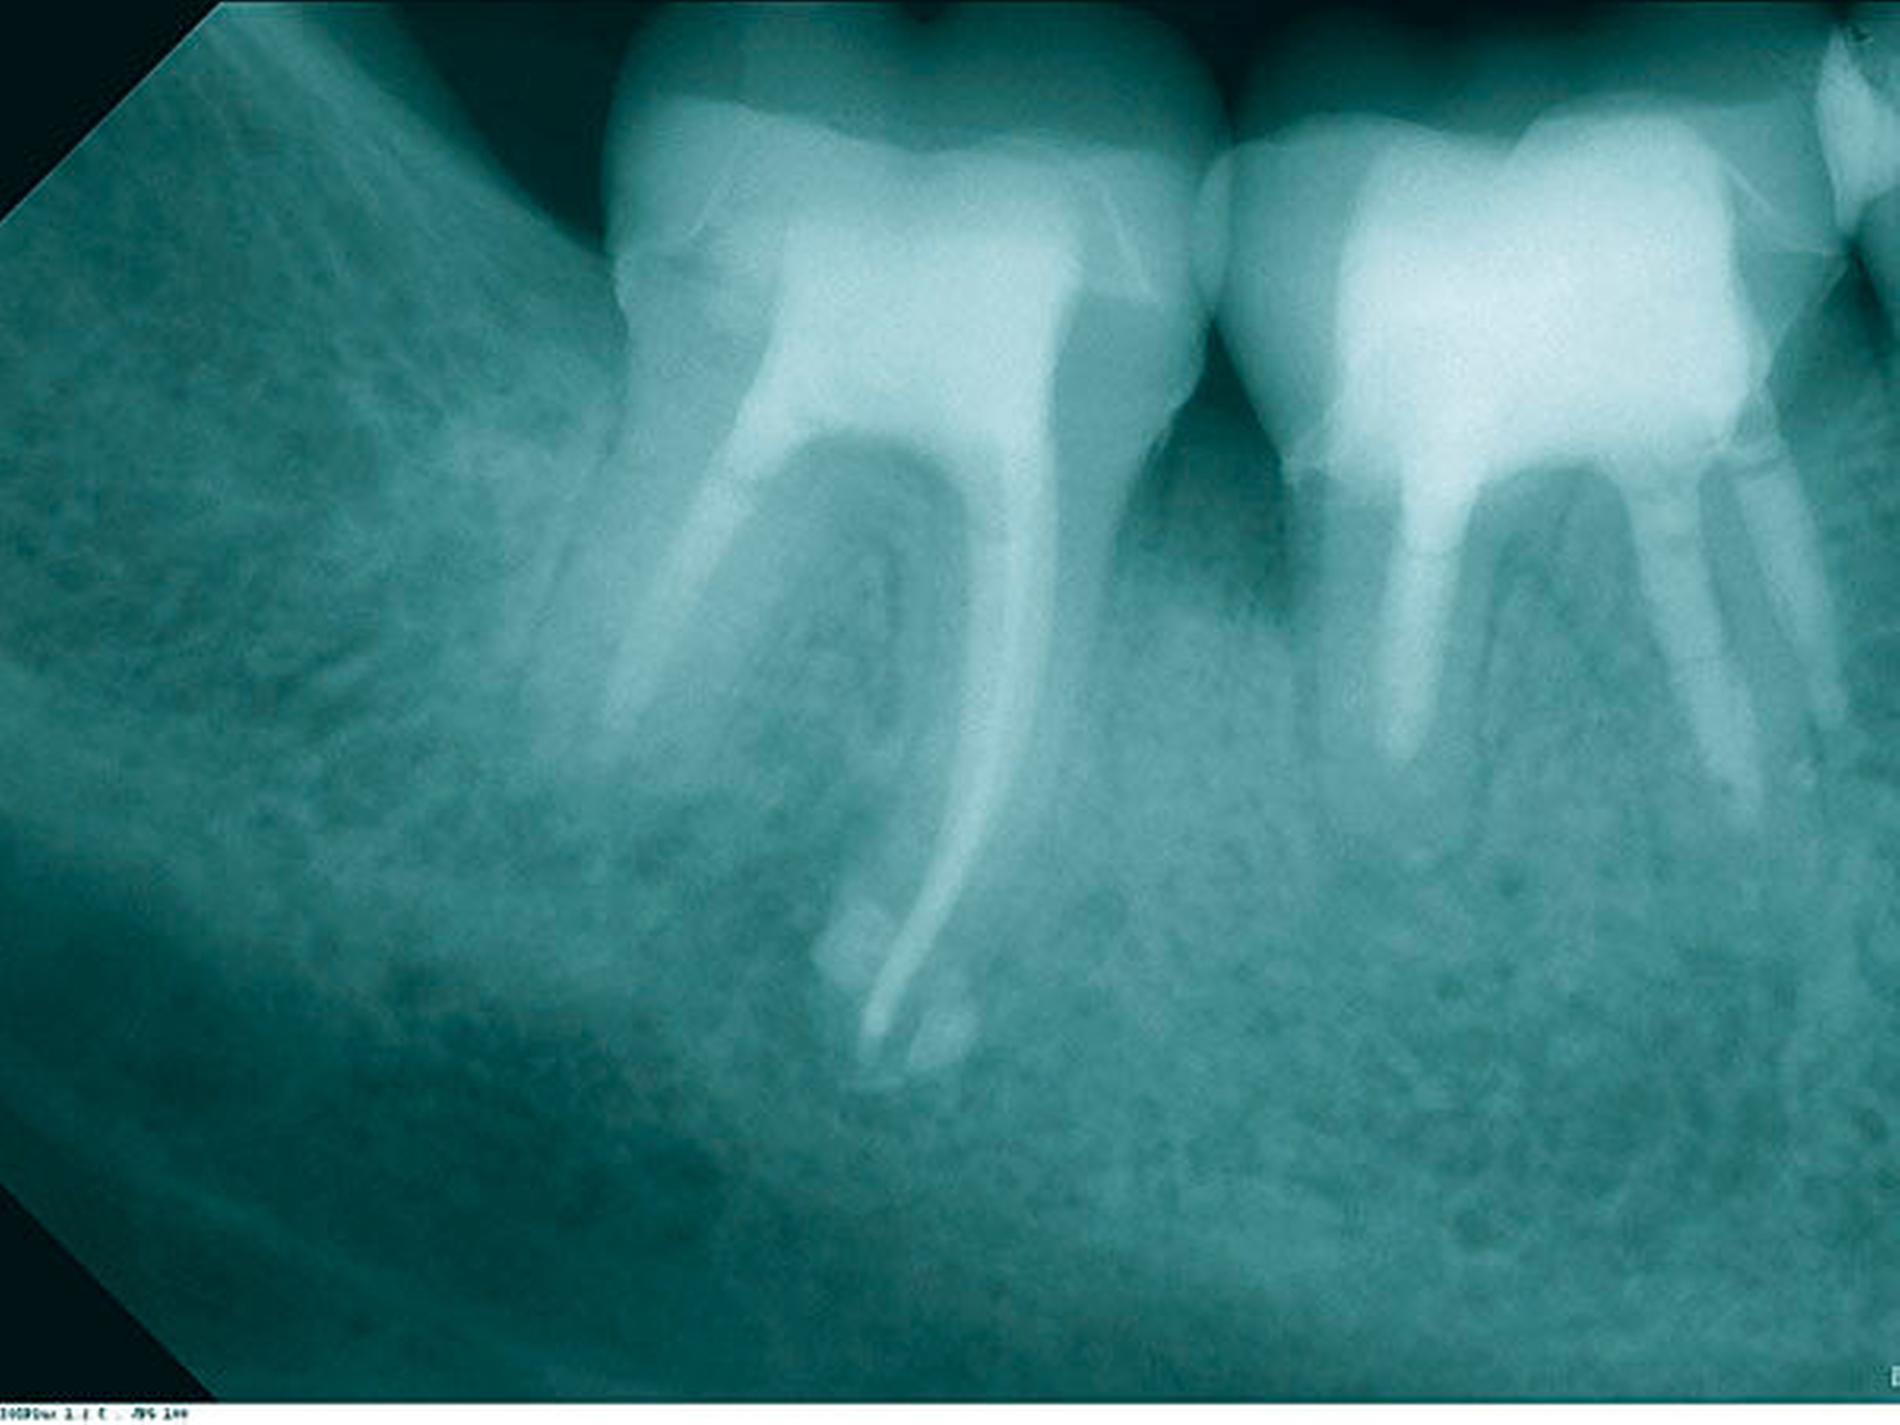

In der ersten Sitzung erfolgten die Trepanation des Zahnes 46 und die komplette Entfernung der Guttapercha unter Kofferdam (Abbildung 11). Nach ausgiebiger Desinfektion mit NaOCl 5 Prozent und EDTA 17 Prozent sowie Schallaktivierung mittels EDDY-Spitzen erfolgte eine medikamentöse Einlage mit AH Temp. In der zweiten Sitzung wurden nach der endometrischen Ermittlung der Arbeitslänge (mesiobukkal 15 mm, mesiolingual 14 mm und distal 13,5 mm) die Kanäle manuell bis ISO 70 aufbereitet. In alle drei Kanäle wurden dann apikale Plugs mit ProRoot MTA (DentsplySirona, Bensheim) eingebracht und diese radiologisch kontrolliert (Abbildung 12). Im Anschluss wurden die koronalen Kanalanteile und die Zugangskavität mit dual-härtendem Komposit verschlossen. Danach wurde die orthograde Revision an Zahn 47 durchgeführt, wobei der anresorbierte distale Kanal ebenfalls mit MTA verschlossen wurde. Abbildung 13 zeigt die Kontrollaufnahme der beiden Zähne nach der Behandlung. Die Nachkontrollen nach neun und 18 Monaten zeigen einen deutlichen Rückgang der Läsionen (Abbildungen 14 und 15) und die Zähne waren symptomfrei. Jedoch kam es zu einer Zunahme der distalen parodontalen Tasche an 46.